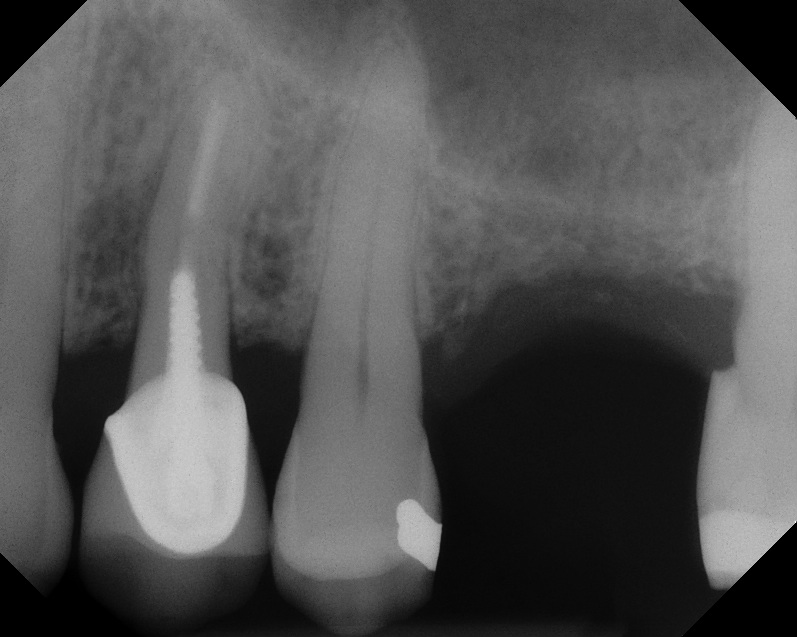

Case 1. Preoperative radiograph showing a ridge height of about 2 mm to 3 mm in the No. 14 position.

Fig. 13

A 74-year-old man presented with only about 2 mm to 3 mm of native bone below the sinus in the No. 14 position (Figure 13). The composite graft used was an approximately 50:50 mixture of DFDBA (Bio-Oss®, Geistlich Biomaterials, www.bio-oss.com) with the addition of about 40% calcium sulfate by volume (Figure 14). The implant placed (Figure 15) was a 10-mm long, rough-surfaced, platform-shifting implant (tapered 4.2 mm to 2.8 mm), and the sinus was raised about 8 mm. The postoperative radiograph taken at 4 months (Figure 16) showed some shrinkage of the graft, but no demarcation of the old sinus floor in the area.